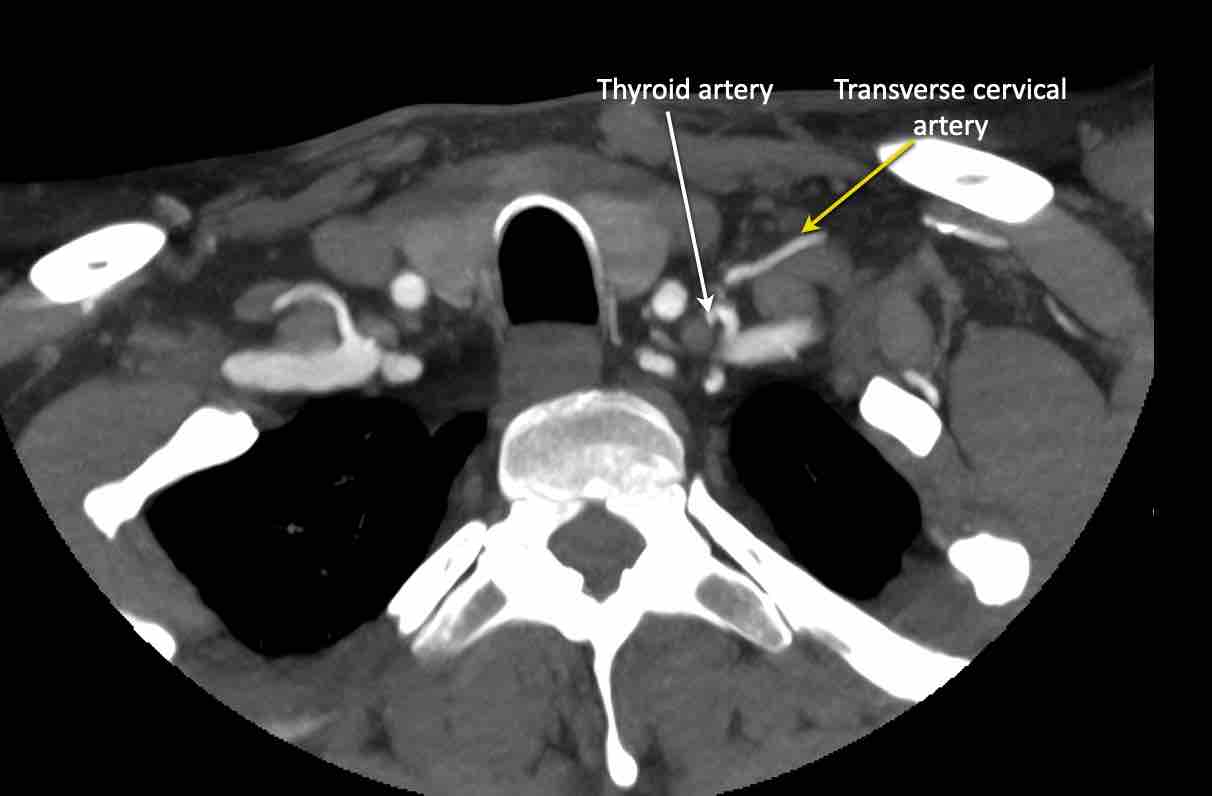

Động mạch cổ ngang

Cuộn qua các hình ảnh để xem giải phẫu của động mạch cổ ngang.